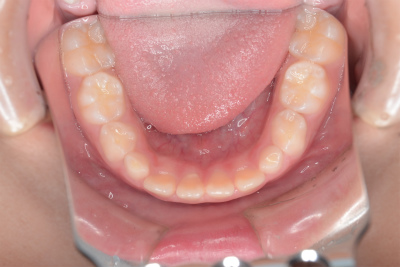

小学3年生